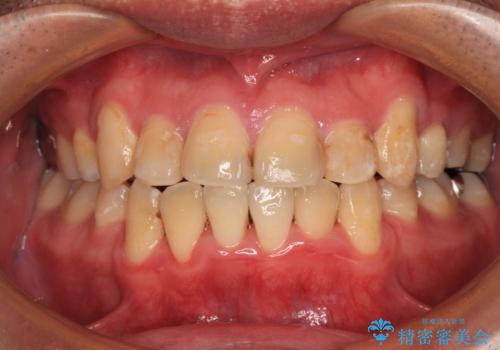

- 前歯の歯並びやむし歯治療の跡、奥歯の銀歯を気にして来院された患者様です。

インビザラインによる矯正治療の後に虫歯や銀歯をセラミックにて補綴することとしました。

前歯のむし歯治療の跡や奥歯の目立つ銀歯がなくなり、明るい口元になりました。